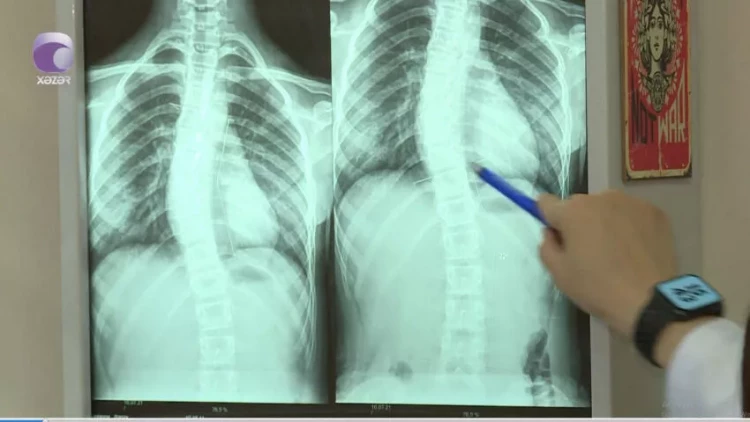

Son zamanlar “8-12” yaş arası uşaqlarda bel və boyun ağrılarının səbəbi

"Son zamanlar 8-12 yaş aralığındakı uşaqlarda bel və boyun ağrıları ilə bağlı şikayətlər nəzərəçarpacaq dərəcədə artıb.

Halbuki, illər öncə uşaqlarda belə problemlər olmurdu. Bunu fizioterapevt Səidə Kərimova "Xəzər xəbər"ə müsahibəsində deyib.

meqale.com xəbər verir ki, həkim səbəb olaraq bildirdi ki, uşaqların çantaları kifayət qədər ağırdır. Çiyin ağrıları isə xüsusən ona görə yaranır ki, ağır çantaları daşıyarkən, kəmərləri uşağın yumşaq toxumasını sıxıb kəsir.

Həkim bildirdi ki, bu yaşda uşaqlar oturanda, xüsusilə də dərs oxuyarkən, qamətini dik tutmalıdır.